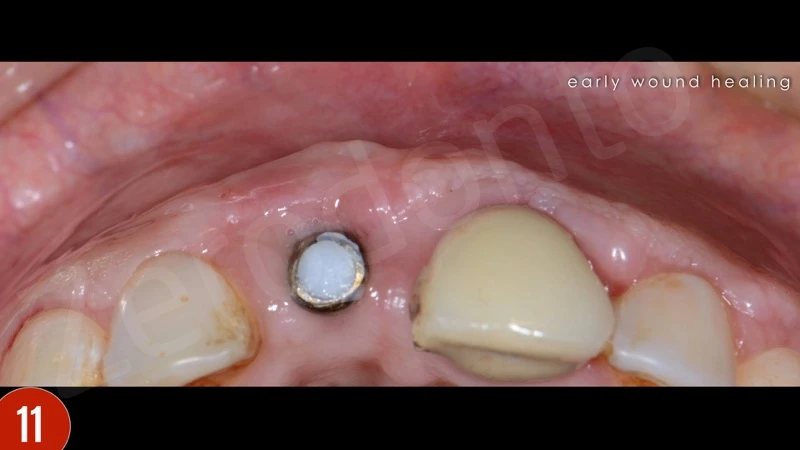

Sự lành thương sớm và tăng độ dày niêm mạc phía môi là thích hợp. Ba tháng sau khi phẫu thuật nha chu, bệnh nhân báo cáo có lỗ rò ở vùng đỉnh răng 21. Đo độ sâu thăm khám là 2-3 mm. Do răng không vừa khít, và lực nhai quá mức, một gãy xương ở vùng chóp đã gặp phải. Bệnh nhân được giải thích cần nhổ răng. Bệnh nhân đã quyết định cấy ghép tức thì.